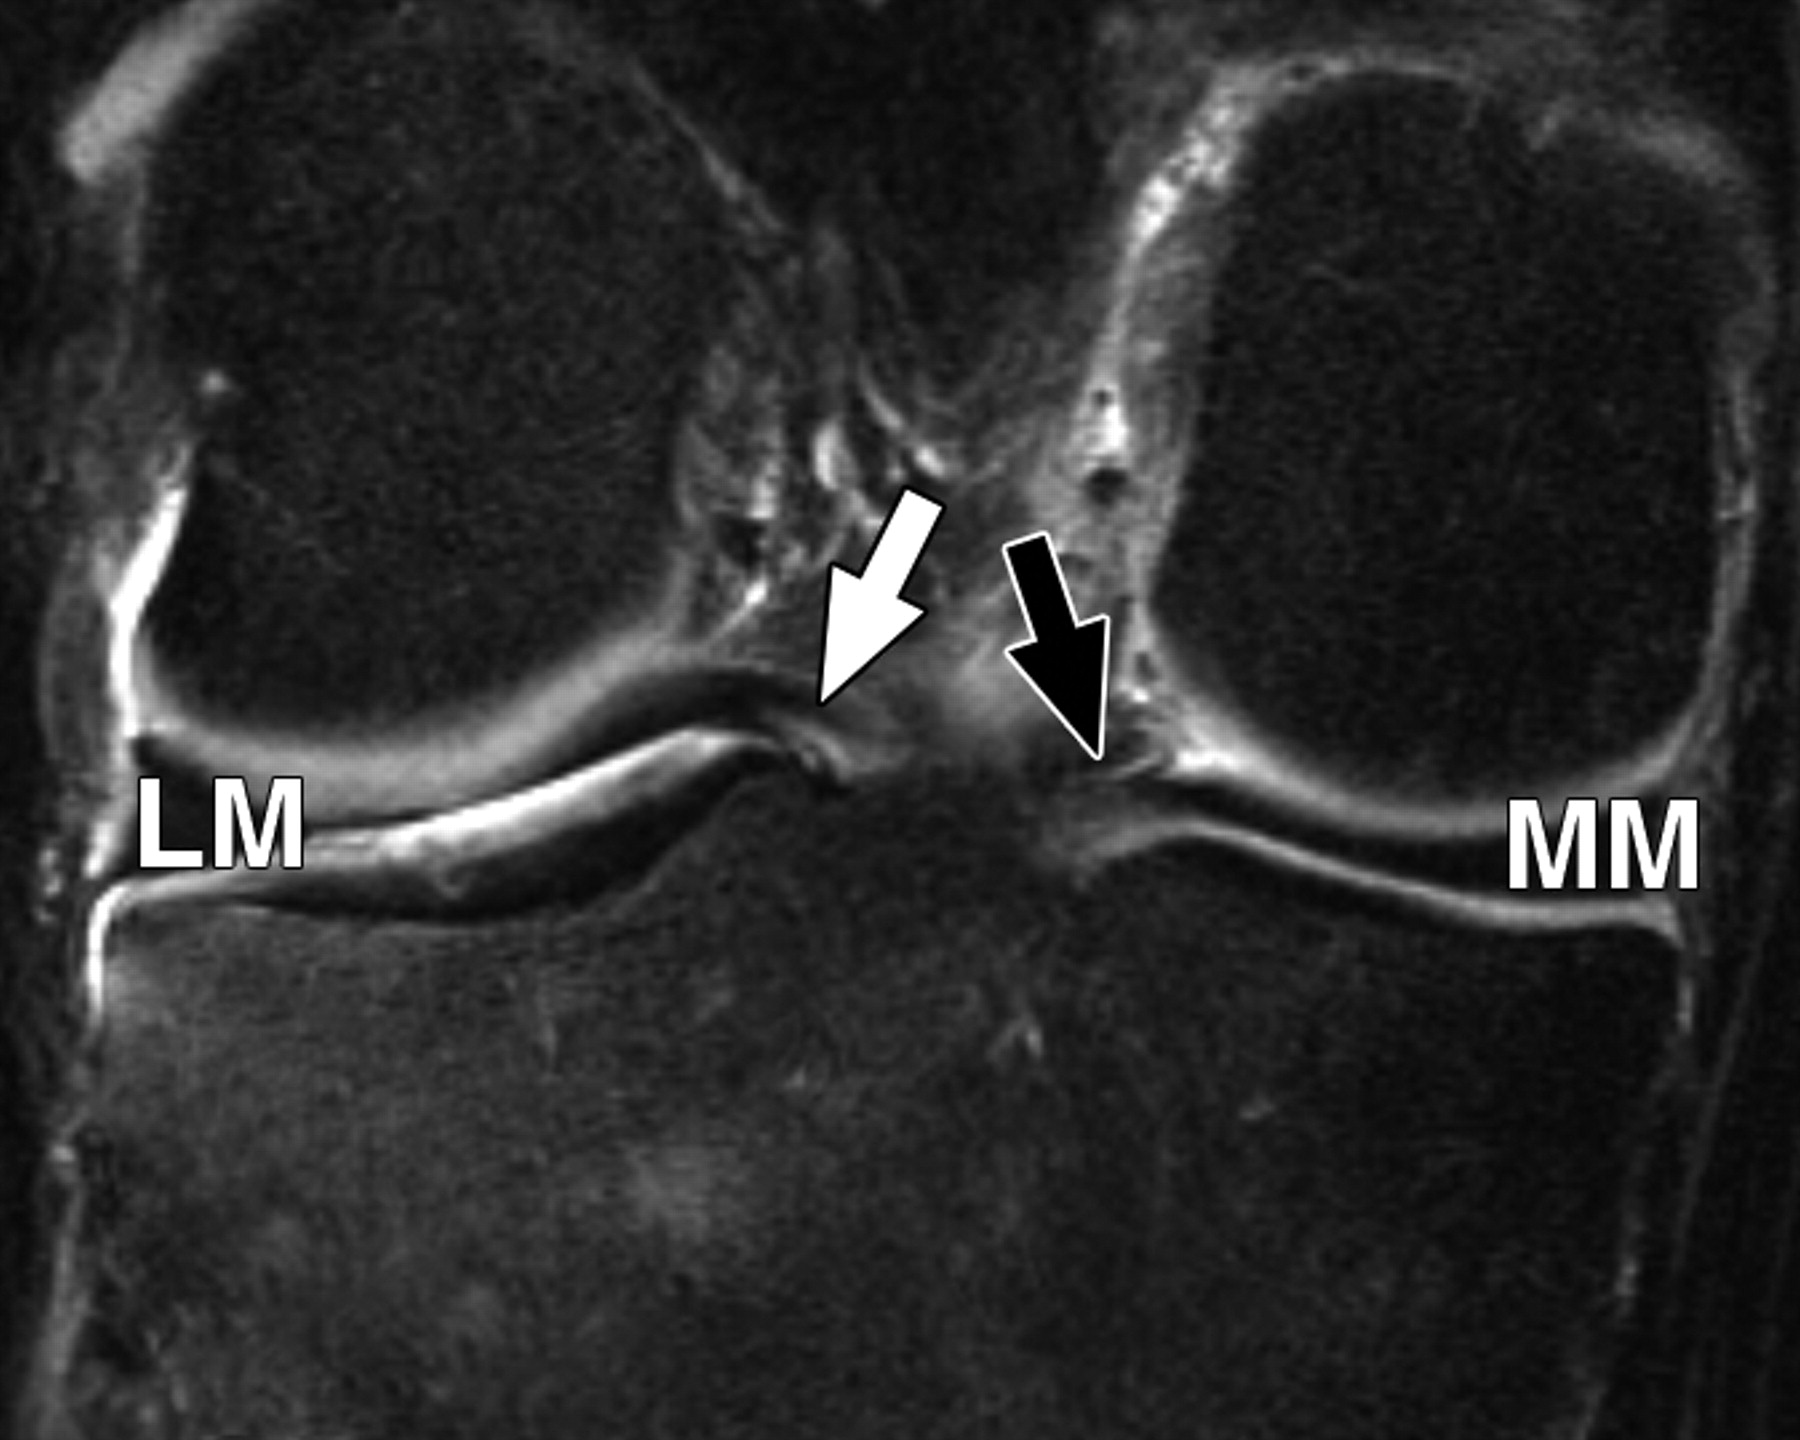

5520cf3c3107bcbe16a450c0ac30f232.jpeg

图5 B-59岁男性。中等加权、脂肪饱和、快速自旋回波(TR/TE有效值,3,700/29)3-T MR图像显示半月板后根和交叉韧带的解剖关系。

冠状面图像依次位于A的腹侧,显示外侧半月板后根(LM)(白色箭头)和内侧半月板后根(MM)(黑色箭头,B)的插入,覆盖后髁间区域的一个以上切片厚度。MT =胫骨内侧结节。